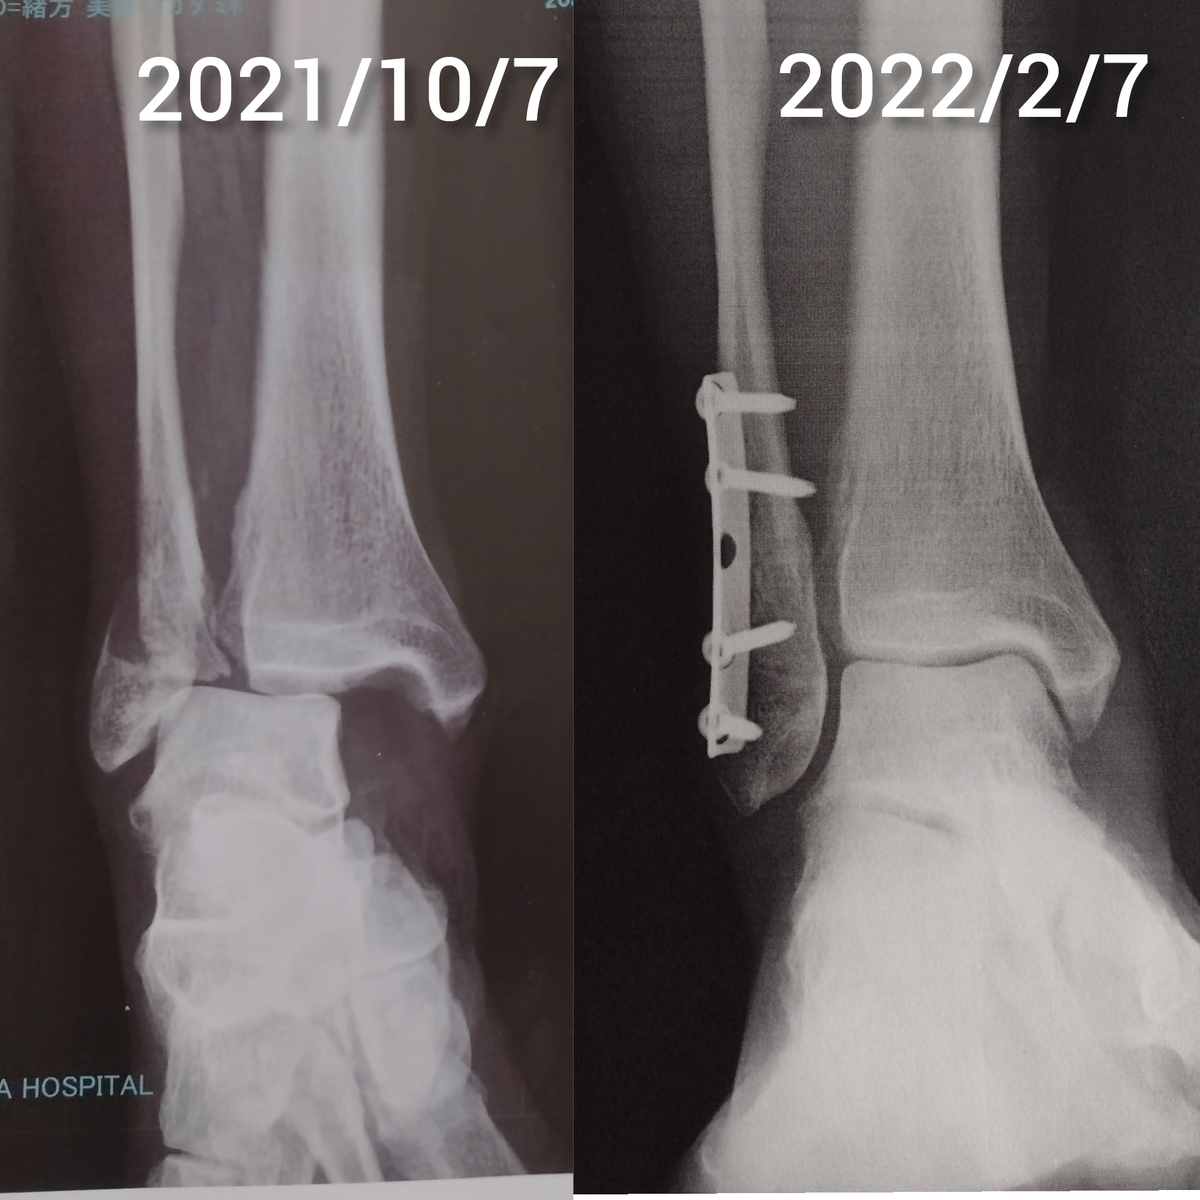

今日は骨折から4カ月の記念日(?)笑笑

12月に脛骨と腓骨を固定していたスクリューを抜き、20日に診察に行った以来の診察日でした。

診察はいつものようにレントゲンから。今までは台に横になって前からと横からの写真を撮っていましたが、今回はそれに加えて立位で荷重をかけて正面から撮影。

「骨はキレイだよ。ちゃんとくっついてる」と言われ思わず「よしっ」と小さくガッツポーズ笑笑

記念(何の?)に荷重して撮影したレントゲンを印刷してもらい診察終了。

次は4月!左右を比べるために両足レントゲンを撮るそうです。